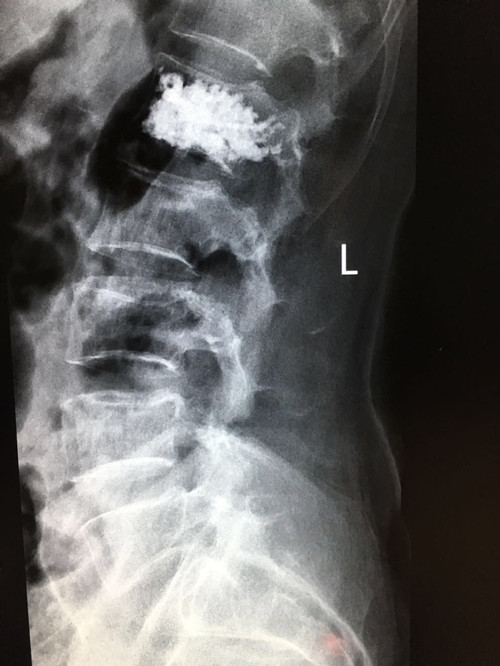

DSA下椎体成形术

一腰痛患者在我院做磁共振检查时发现为腰椎血管瘤,于7月5日下午在DSA下行椎体成形术,手术顺利精准,术后疼痛立即缓解,病人恢复非常好,家属对我院骨科的技术及服务非常满意。